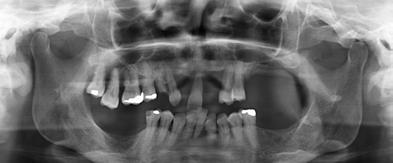

Figura 2. Imagen radiográfica inicial ósea en la mayoría de los dientes, con un defecto horizontal predominante y varios defectos en cuña en dientes aislados. Figura 3-6. Imágenes de la paciente, portadora de una prótesis removible para las ausencias dentarias presentes, que como vemos se encuentra completamente desadaptada además de con una estética poco adecuada.

2 3 5 7 4 6

Figura 7. En una primera fase se llevan a cabo las extracciones de las piezas que no pueden mantenerse debido a la gran movilidad que presentan y se colocan prótesis provisionales sobre los dientes remanentes que se han conservado tras un buen tratamiento periodontal.

Figura 8-11. Imágenes de la planificación del cone-beam dentral tras el cierre de los tejidos blandos (inserción temprana de los implantes). En ellos observamos la planificación de los implantes de 6.5 mm de longitud y de diámetro reducido y plataforma 3.0 que van a ser empleados.

Dentista y Paciente 18 Calidad y dirección

12 13 14 15 16

Figuras 14-16. Abordaje quirúrgico inicial con la extracción de las piezas remanentes superiores, la inserción de los implantes y la carga inmediata de los mismos. Figuras 12-13. Segundo abordaje quirúrgico superior donde se insertan implantes en zonas donde en la primera fase no fue posible y la colocación de los implantes inferiores. En el corte de control superior observamos la correcta integración de uno de los primeros implantes colocados.